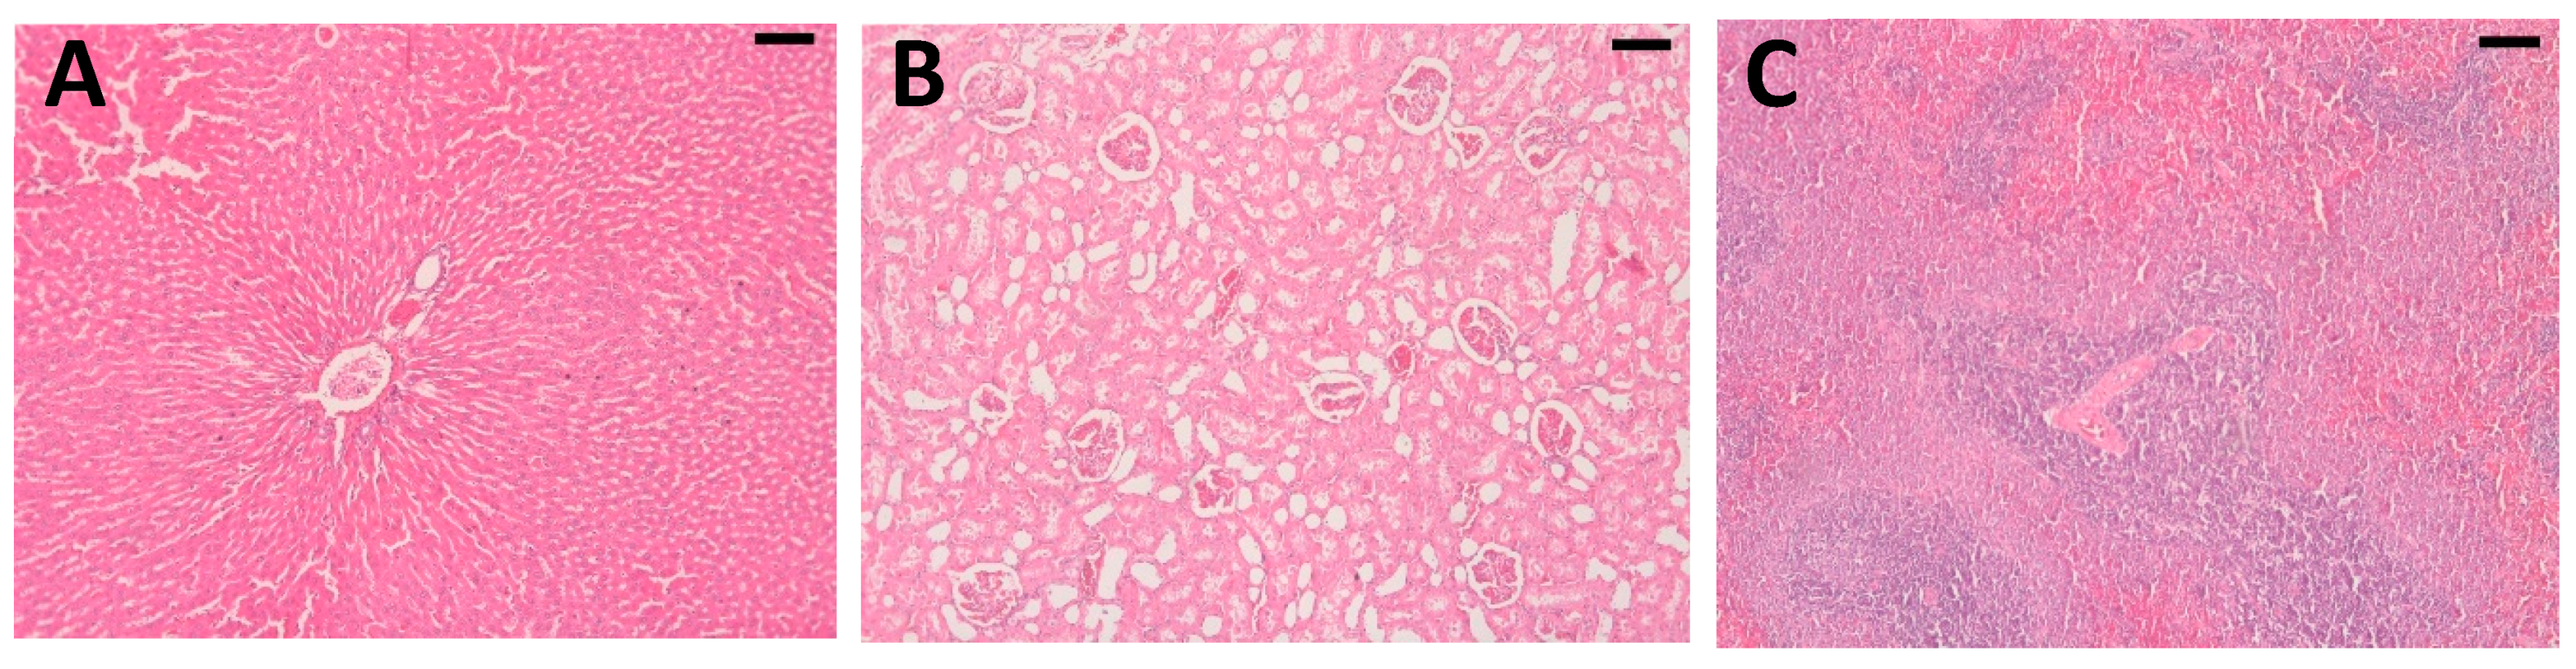

2.4. Histopathological Analysis

4.5. Histopathological Analysis of Articular Cartilage